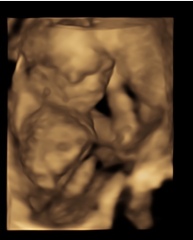

I went for an ultrasound the other day (16 weeks) and can’t seem to stop noticing on the images they’ve given me there seems to be little brown marks all over him. Are these birth marks or something else?

Birthmark on 4D ultrasound??